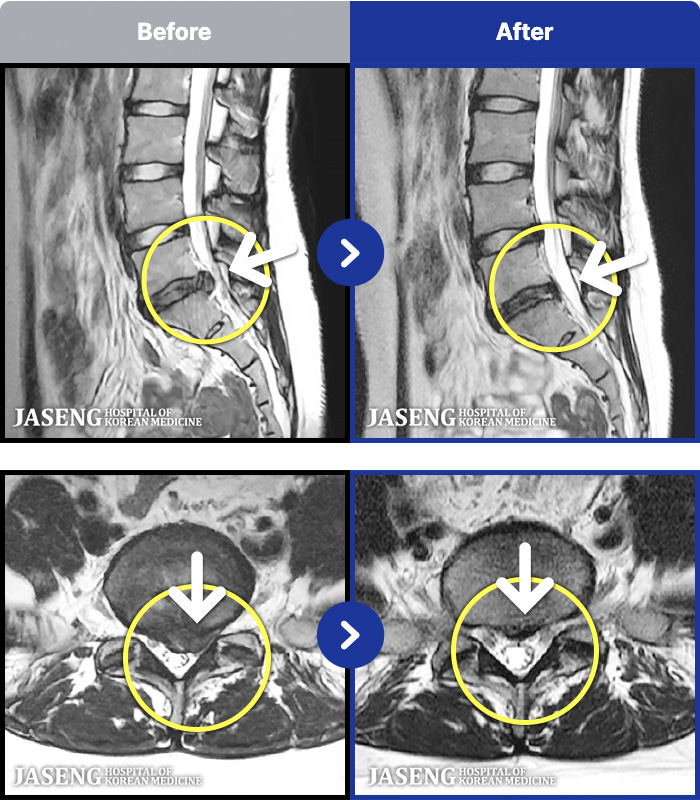

ȯںп Ǹ ǿ ԿǾ, ο ġ ۿ Ƿ ġḦ Ͻñ ٶϴ.